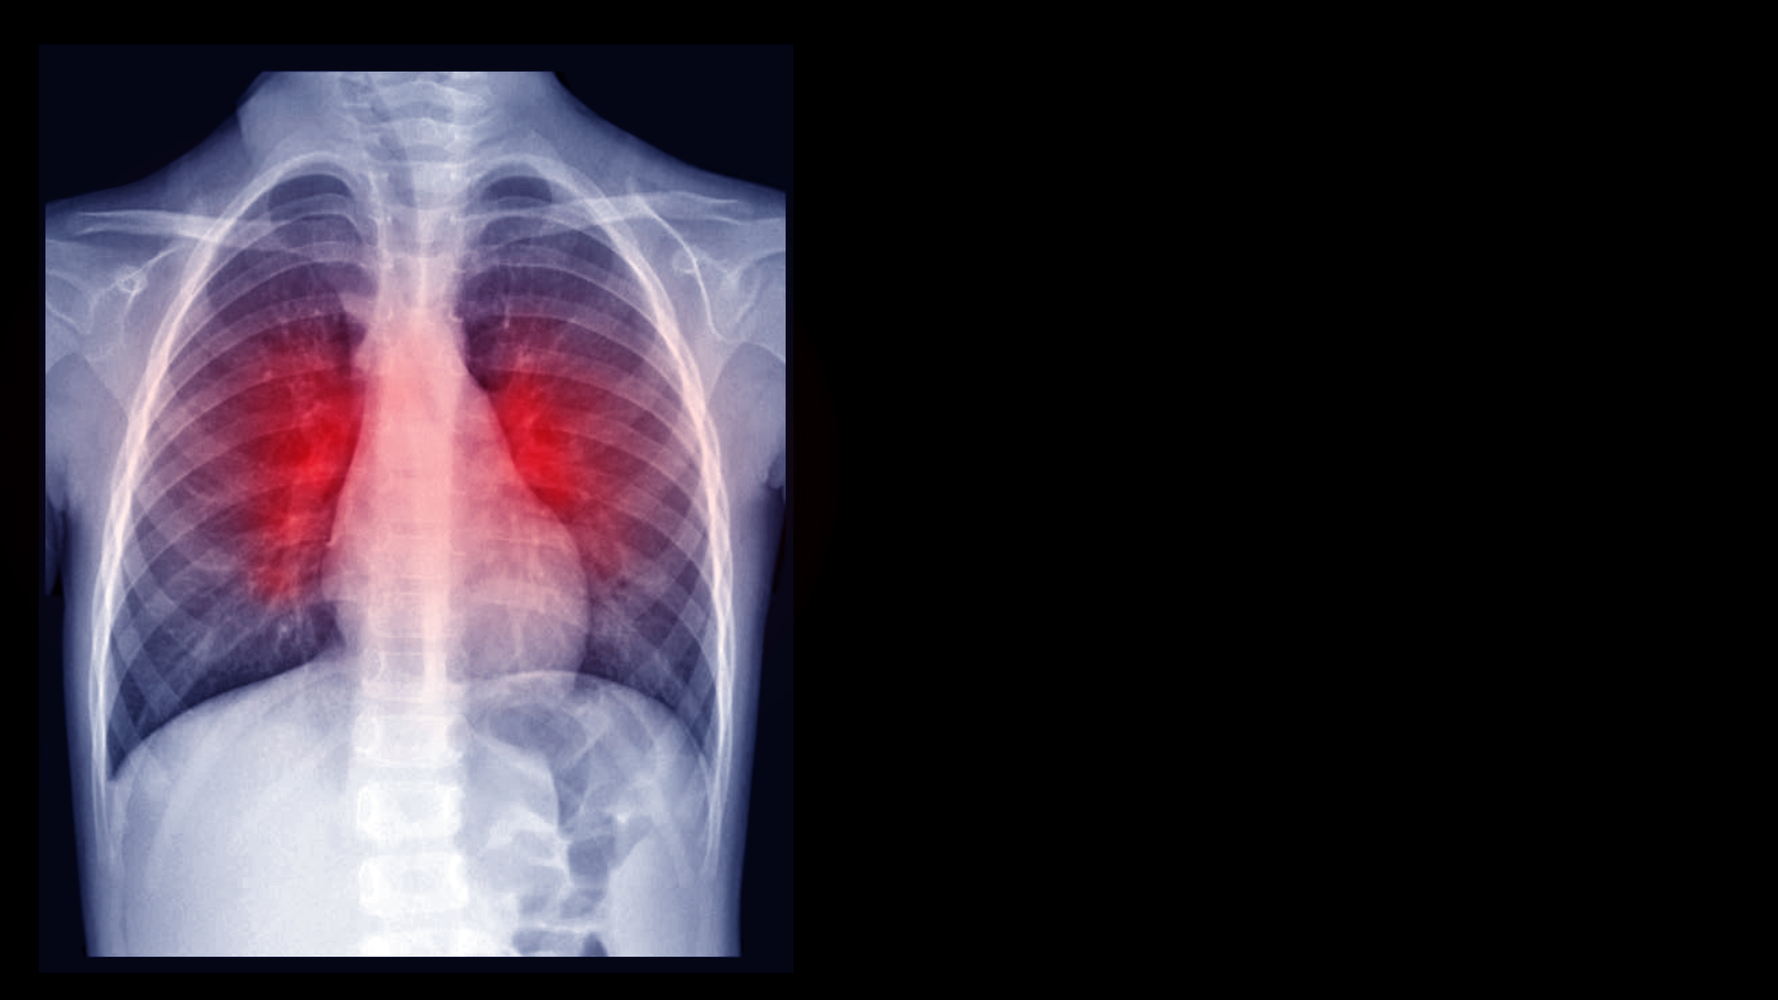

Bronchiectasis is a chronic lung condition that can significantly impact one’s quality of life. Recognizing the early warning signs is crucial for timely diagnosis and treatment. This article will explore some of the key bronchiectasis breathing symptoms that you should be aware of to ensure you seek medical attention when necessary.